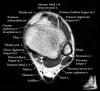

발목 관절의 MRI 단면 영상

- Axial section

Axial PD fat suppression evaluates the tendons and ligaments of the ankle particularly after acute/subacute injuries. It also is sensitive to talar dome osteochondral defects. Alternatively, a T2 sequence can be used to eliminate magic angle artifact that may occur as the tendons travel around the malleolar turns.

Tibiofibular ligaments

Lateral ankle ligaments

Deltoid and spling ligaments

Tendon(Achilles, Medial, Lateral, Anterior)